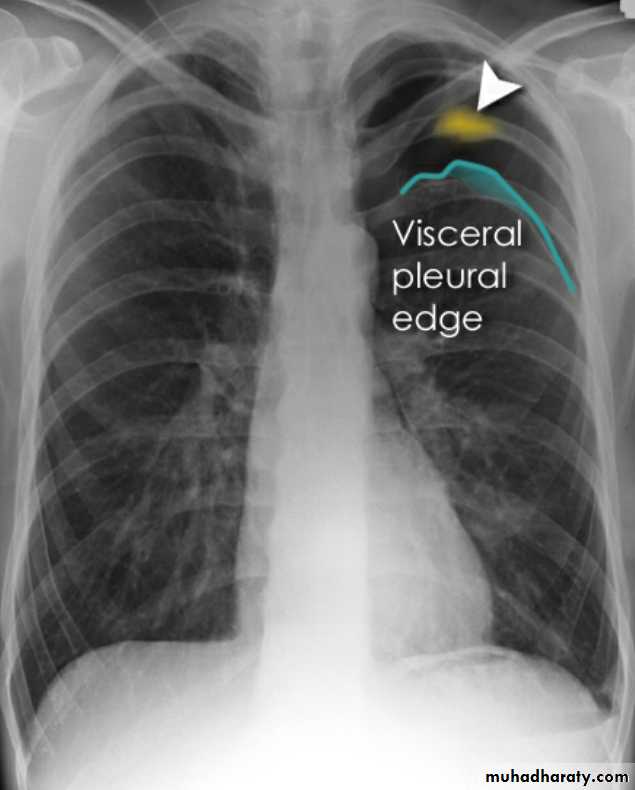

PneumothoraxPneumothorax refers to the presence of gas (air) in the pleural space. When this collection of gas is constantly enlarging with resulting compression of mediastinal structures it can be life-threatening and is known as a tension pneumothorax

A pneumothorax is, when looked for, usually relatively easily appreciated. Typically they demonstrate:

visible visceral pleural edge see as a very thin, sharp white line

no lung markings are seen peripheral to this line

the peripheral space is radiolucent compared to adjacent lung

the lung may completely collapse

the mediastinum should not shift away from the pneumothorax unless a tension pneumothorax is present